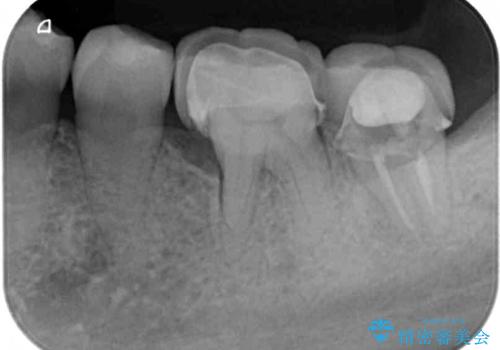

- 左下奥のクラウンに違和感を感じるとのことで来院された患者様です。

最後方歯は歯槽骨よりも深い部分にまでむし歯が及んでおり、患者様と相談の上、インプラントによる補綴治療を行うこととしました。

根尖部の病変が小さいことから抜歯即時埋入が選択されるところですが、抜歯窩洞が大きくなることと、窩洞直下に神経や血管が走行していることから、抜歯してから2,3ヶ月待機してから埋入することとしました。